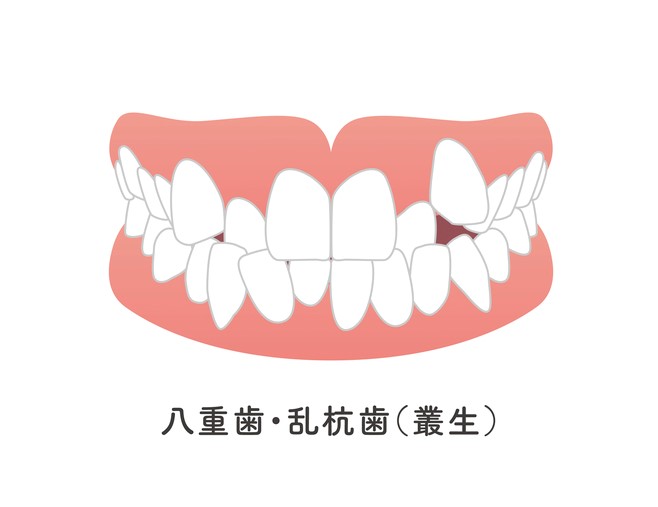

ガチャ歯(叢生)を治したい!費用や治療期間について

【表側矯正症例】叢生(歯並びの凸凹)と前歯で噛めるようになりたい!

【表側矯正症例】歯の叢生(凸凹)が気になる・交叉咬合